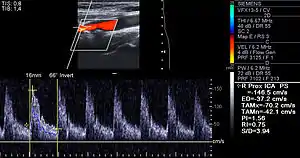

Besides the traditional diagnostic methods such as angiography and stress-testing, other detection techniques have been developed in the past decades for earlier detection of atherosclerotic disease. Some of the detection approaches include anatomical detection and physiologic measurement.

Examples of anatomical detection methods include coronary calcium scoring by CT, carotid IMT (intimal media thickness) measurement by ultrasound, and intravascular ultrasound (IVUS). Examples of physiologic measurement methods include lipoprotein subclass analysis, HbA1c, hs-CRP, and homocysteine. Both anatomic and physiologic methods allow early detection before symptoms show up, disease staging, and tracking of disease progression. Anatomic methods are more expensive and some of them are invasive in nature, such as IVUS. On the other hand, physiologic methods are often less expensive and safer. But they do not quantify the current state of the disease or directly track progression. In recent years, developments in nuclear imaging techniques such as PET and SPECT have provided ways of estimating the severity of atherosclerotic plaques.[78]